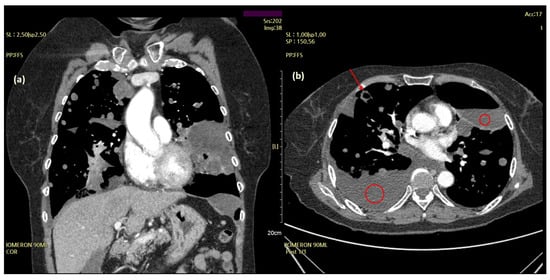

Subsequently, the patient experienced two more episodes of recurrent dyspnea owing to increased pleural effusion within the two years following the initial onset of symptoms. A chest CT performed at the time of the third hospitalization for acute dyspnea in June 2019 revealed large and multiple hydropneumothoraces and bullae with massive bilateral pleural effusions (Figure 2).

Figure 2.

Chest computed tomography (CT) features of the aggravating lesions. Cystic masses (arrow) and large and multiple hydropneumothoraces with massive pleural effusion (red circles) on chest CT (June 2019). (a) Coronal and (b) axial views.

The size and distribution of the pulmonary masses were aggravated along with cystic changes. Considering the rapid growth in a relatively short time and associated distressing symptoms, the decision was made to initiate active antitumor treatment instead of continuing with conservative management and close observation. The patient had previously undergone bilateral salpingo-oophorectomy and was menopausal. Therefore, letrozole, an aromatase inhibitor, was initiated at 2.5 mg once daily. At this time, considering the patient’s aggressive and rapid clinical progression, which was not considered benign, the possibility of malignancy, rather than BML, was raised. Therefore, it was decided to review the surgical specimens of the lung and pelvic masses from 2017. Microscopic examination revealed that the metastatic lung nodules were small, uniform, characterized by bland tumor cells with spindled nuclei and scant cytoplasm, in the background of rich small arterioles or capillary networks (Figure 3). Mitotic counts were up to 1 per high-power field. Necrosis was not present.